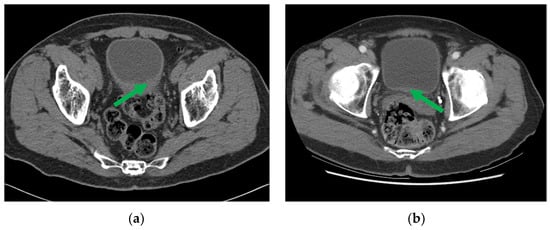

One example of pre- and post-chemotherapy CTU scans of bladder cancer can be found in Figure 3. The CTU scans used in this study were acquired with GE Healthcare LightSpeed MDCT scanners, Issaquah, WA, USA, set at 120 kVp and 120–280 mA, with the slice interval ranging from 0.625 to 5 mm. The CTU series with the comparatively best quality were utilized regardless of whether they were performed after administration of contrast material or were non-contrast images. The contrast-enhanced CTU scans were obtained 12 min after the initiation of the first bolus of a split-bolus IV contrast injection, and 2 min after the initiation of the second bolus of 175 mL of nonionic contrast material at a concentration of 300 mg iodine/ml.

Figure 3. CTU images of a bladder cancer patient (a) pre- and (b) post-neoadjuvant chemotherapy, with the initial and residual cancer indicated by the green arrow.